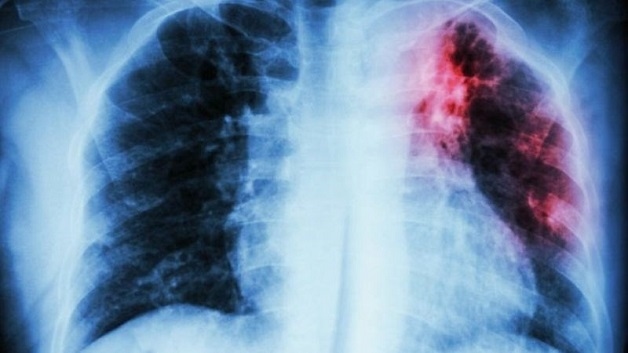

Hình ảnh minh họa phổi nhiễm vi khuẩn lao